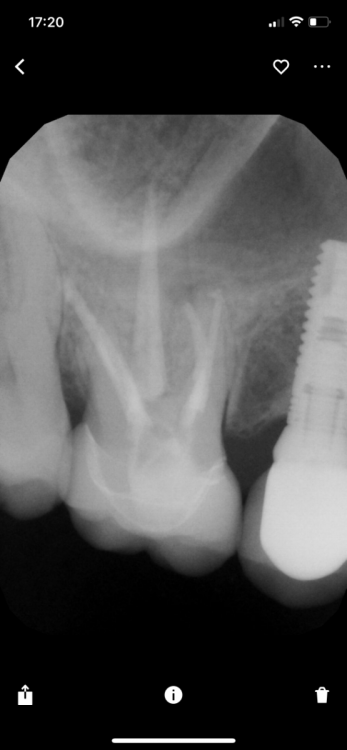

NazranDantist Опубликовано 4 мая, 2022 Поделиться Опубликовано 4 мая, 2022 Всем привет. Если честно, попади ко мне этот пациент, первым делом отправил бы на реэндо, сказав, что предыдущий доктор немного не доработал?. Нельзя такое показывать, щас начинающие специалисты решат, что можно в принципе не пломбировать канал до апекса, чтобы сохранить витальность пульпы, или просто оправдывать свое неумение или нехотение в работе. Ссылка на комментарий

Гарриевич Опубликовано 4 мая, 2022 Автор Поделиться Опубликовано 4 мая, 2022 6 часов назад, NazranDantist сказал: Всем привет. Если честно, попади ко мне этот пациент, первым делом отправил бы на реэндо, сказав, что предыдущий доктор немного не доработал?. Нельзя такое показывать, щас начинающие специалисты решат, что можно в принципе не пломбировать канал до апекса, чтобы сохранить витальность пульпы, или просто оправдывать свое неумение или нехотение в работе. Вы бы это сделали, потому что большинство врачей-стоматологов лечат не пациента, а снимки ) но я вас понимаю, без знания протокола того доктора это выглядит стремно для большинства 1 Ссылка на комментарий

NazranDantist Опубликовано 5 мая, 2022 Поделиться Опубликовано 5 мая, 2022 04.05.2022 в 15:07, Гарриевич сказал: Вы бы это сделали, потому что большинство врачей-стоматологов лечат не пациента, а снимки ) но я вас понимаю, без знания протокола того доктора это выглядит стремно для большинства Скорее по данным снимка лечим пациента. Может быть банально, но эффективно? Ссылка на комментарий

Гарриевич Опубликовано 7 мая, 2022 Автор Поделиться Опубликовано 7 мая, 2022 05.05.2022 в 07:02, annda сказал: Как вы контролируете витальность в отсроченной перспективе? саму витальность никак оценивать возможно только состояние периапикальный тканей по прицельным и кт Ссылка на комментарий